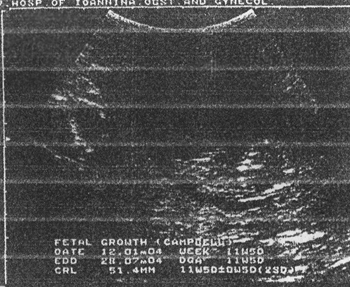

CRL (εικόνα 1)

Στη μέτρηση του CRL μπορεί να προκύψουν διαφορές μεταξύ των υπερηχογραφιστών. Διαφορές μέχρι της τάξεως των 1.2mm και αντίστοιχα 3-5 ημερών στην ηλικία κύησης μπορεί να οφείλονται και σε διάφορους άλλους λόγους (γενετικούς κ.λπ.).(6,7)

Εικόνα 1. CRL. Κεφαλοουραίο μήκος εμβρύου. Εκτίμηση ηλικίας κύησης 1ου τρίμηνου. Εικόνα 2. BPD. Αμφιβρεγματική διάμετρος κεφαλής εμβρύου. Εκτίμηση ηλικίας κύησης 2ου τριμήνου.

Το CRL είναι ο πιο αξιόπιστος δείκτης ηλικίας κύησης στο 1ο τρίμηνο και πρέπει να αποτελεί σημείο αναφοράς για τη σύγκριση με τους δείκτες του 2ου τριμήνου.